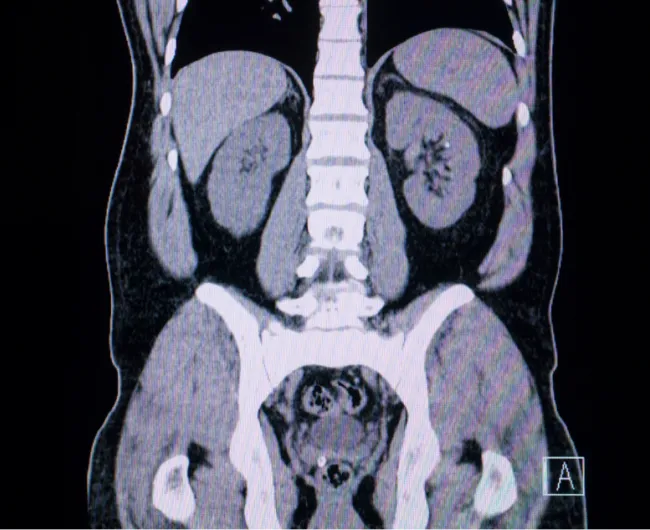

CT Scan | Detect metastases or local recurrence | Imaging | Every 6–12 months | High-resolution internal imaging | Radiation exposure; may miss small lesions |